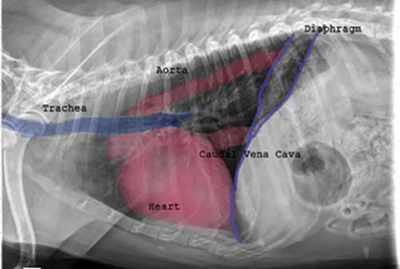

Radiography (x-ray) is used to determine if the heart is enlarged

(particularly the left atrium and left ventricle), if the veins from the

lungs to the heart are distended, or if fluid is beginning to develop in the

lungs.* X-rays also will show any enlargement of

the pulmonary vein, a classic symptom of congestive heart failure (CHF).

• VHS measurements to detect enlargement

Cardiologists use x-rays to evaluate the size and shape of the heart in

order to assess the severity of MVD.

The Vertebral Heart

Size or Scale or Sum (VHS) is an objective means of measuring

heart size.

As

the x-ray image above shows, using calipers, they

measure the length (from the apex to the bottom of the left mainstem) and width

(at

its widest point perpendicular to the lemgth measurement) of the heart

on a lateral x-ray and compare those dimensions

to the number of veterbrae from T4 to T12, to calculate the VHS value. Since

the dog's own vertebrae are used for comparison, each VHS value is

normalized to the dog's overall body size.